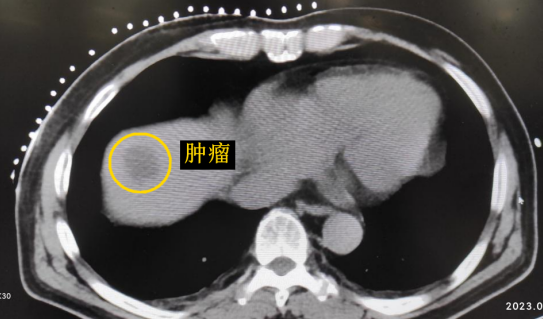

影像診療科陳寶瑩主任團隊評估后指出,較大的腫瘤位于肝頂部緊貼膈肌,如果繼續(xù)發(fā)展,腫瘤很可能突破肝包膜侵犯到膈肌,建議及時干預。病變緊臨膈肌,如果要完全消融,膈肌損傷的可能性就比較大,與其他局部治療方式比較,冷凍消融對周圍臟器、血管及神經(jīng)損傷的可能性較小、安全性更高、患者疼痛感較輕,建議通過CT精準引導下經(jīng)皮微創(chuàng)冷凍消融治療。

這個患者病變位置刁鉆,穿刺難度大,冷凍消融的難點在于既要不損傷膈肌和肺組織,同時又要盡最大可能完全消融腫瘤。術前陳寶瑩主任、李鐵柱教授、兀云飛醫(yī)生詳細設計進針路徑、布針計劃,術中微創(chuàng)團隊協(xié)調(diào)配合,李鐵柱教授仔細操作,精準到位,順利完成兩個病變的布針,遂啟動治療,先快速降溫到-150多度,再升溫至15?,經(jīng)過兩個循環(huán)反復,即刻觀察到病變完全被冰球覆蓋,同時周圍臟器無損傷,術中患者幾乎沒有疼痛,還和醫(yī)生聊起了天。

CT精準定位腫瘤